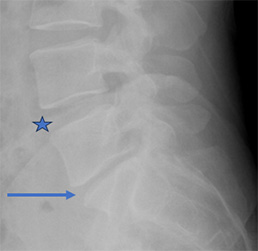

42 year old man with unrelenting low back pain. He has difficulty sitting and feels better laying down. He had done therapy for 6 years and injections without relief. He had a previous discectomy for a disc herniation 15 years ago. Xray shows significant disc degeneration. The height of the disc (arrow) is significantly lower than a normal disc (star).

Because of failure of extensive nonoperative management, patient underwent an anterior lumbar interbody fusion minimally invasively. The disc height was restored.